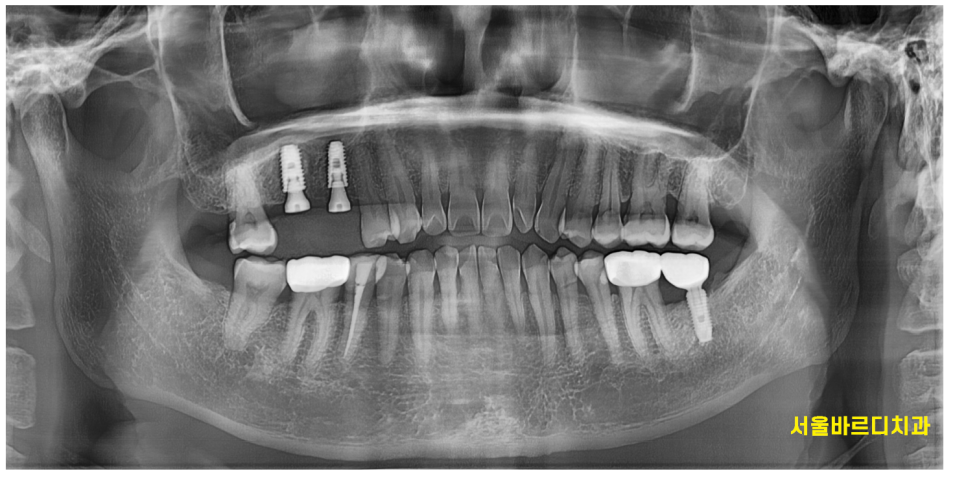

발치 후 1차 뼈이식을 진행하고

6개월이 지나 임플란트 수술을 진행하였습니다.

임플란트를 심고 부족한 뼈는 추가적으로 넣어 이식하고

3개월 정도 더 기다려보았습니다.

240102

약 9개월정도 지나 완성이 되었습니다.